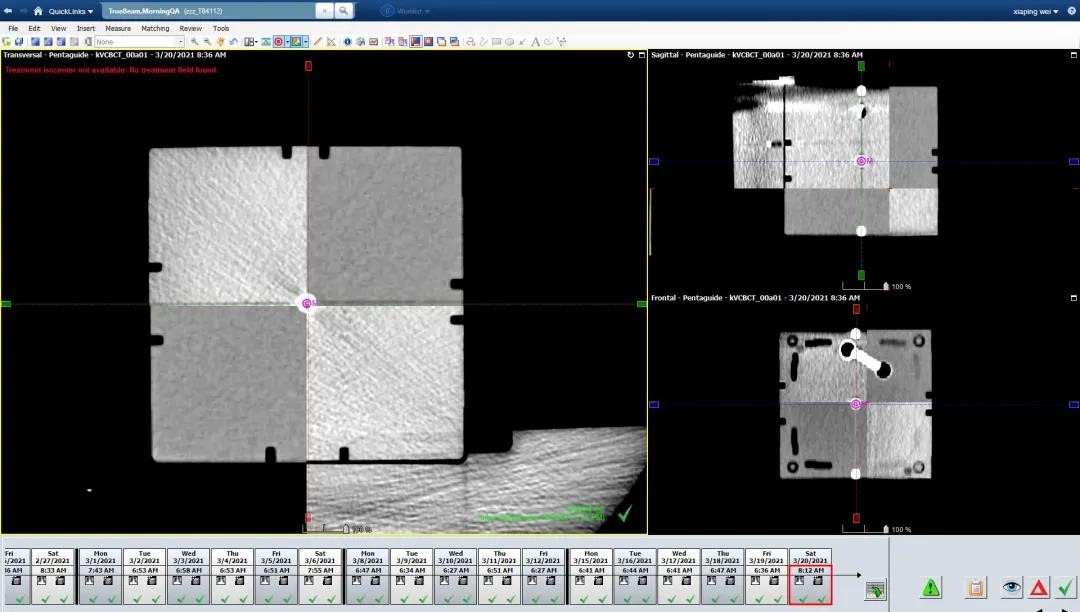

2、每日晨检须做六维床IGRT的精度验证及Winston-Luzt

每日IGRT精度验证

通过Cube中间的同心圆小球检查治疗等中心